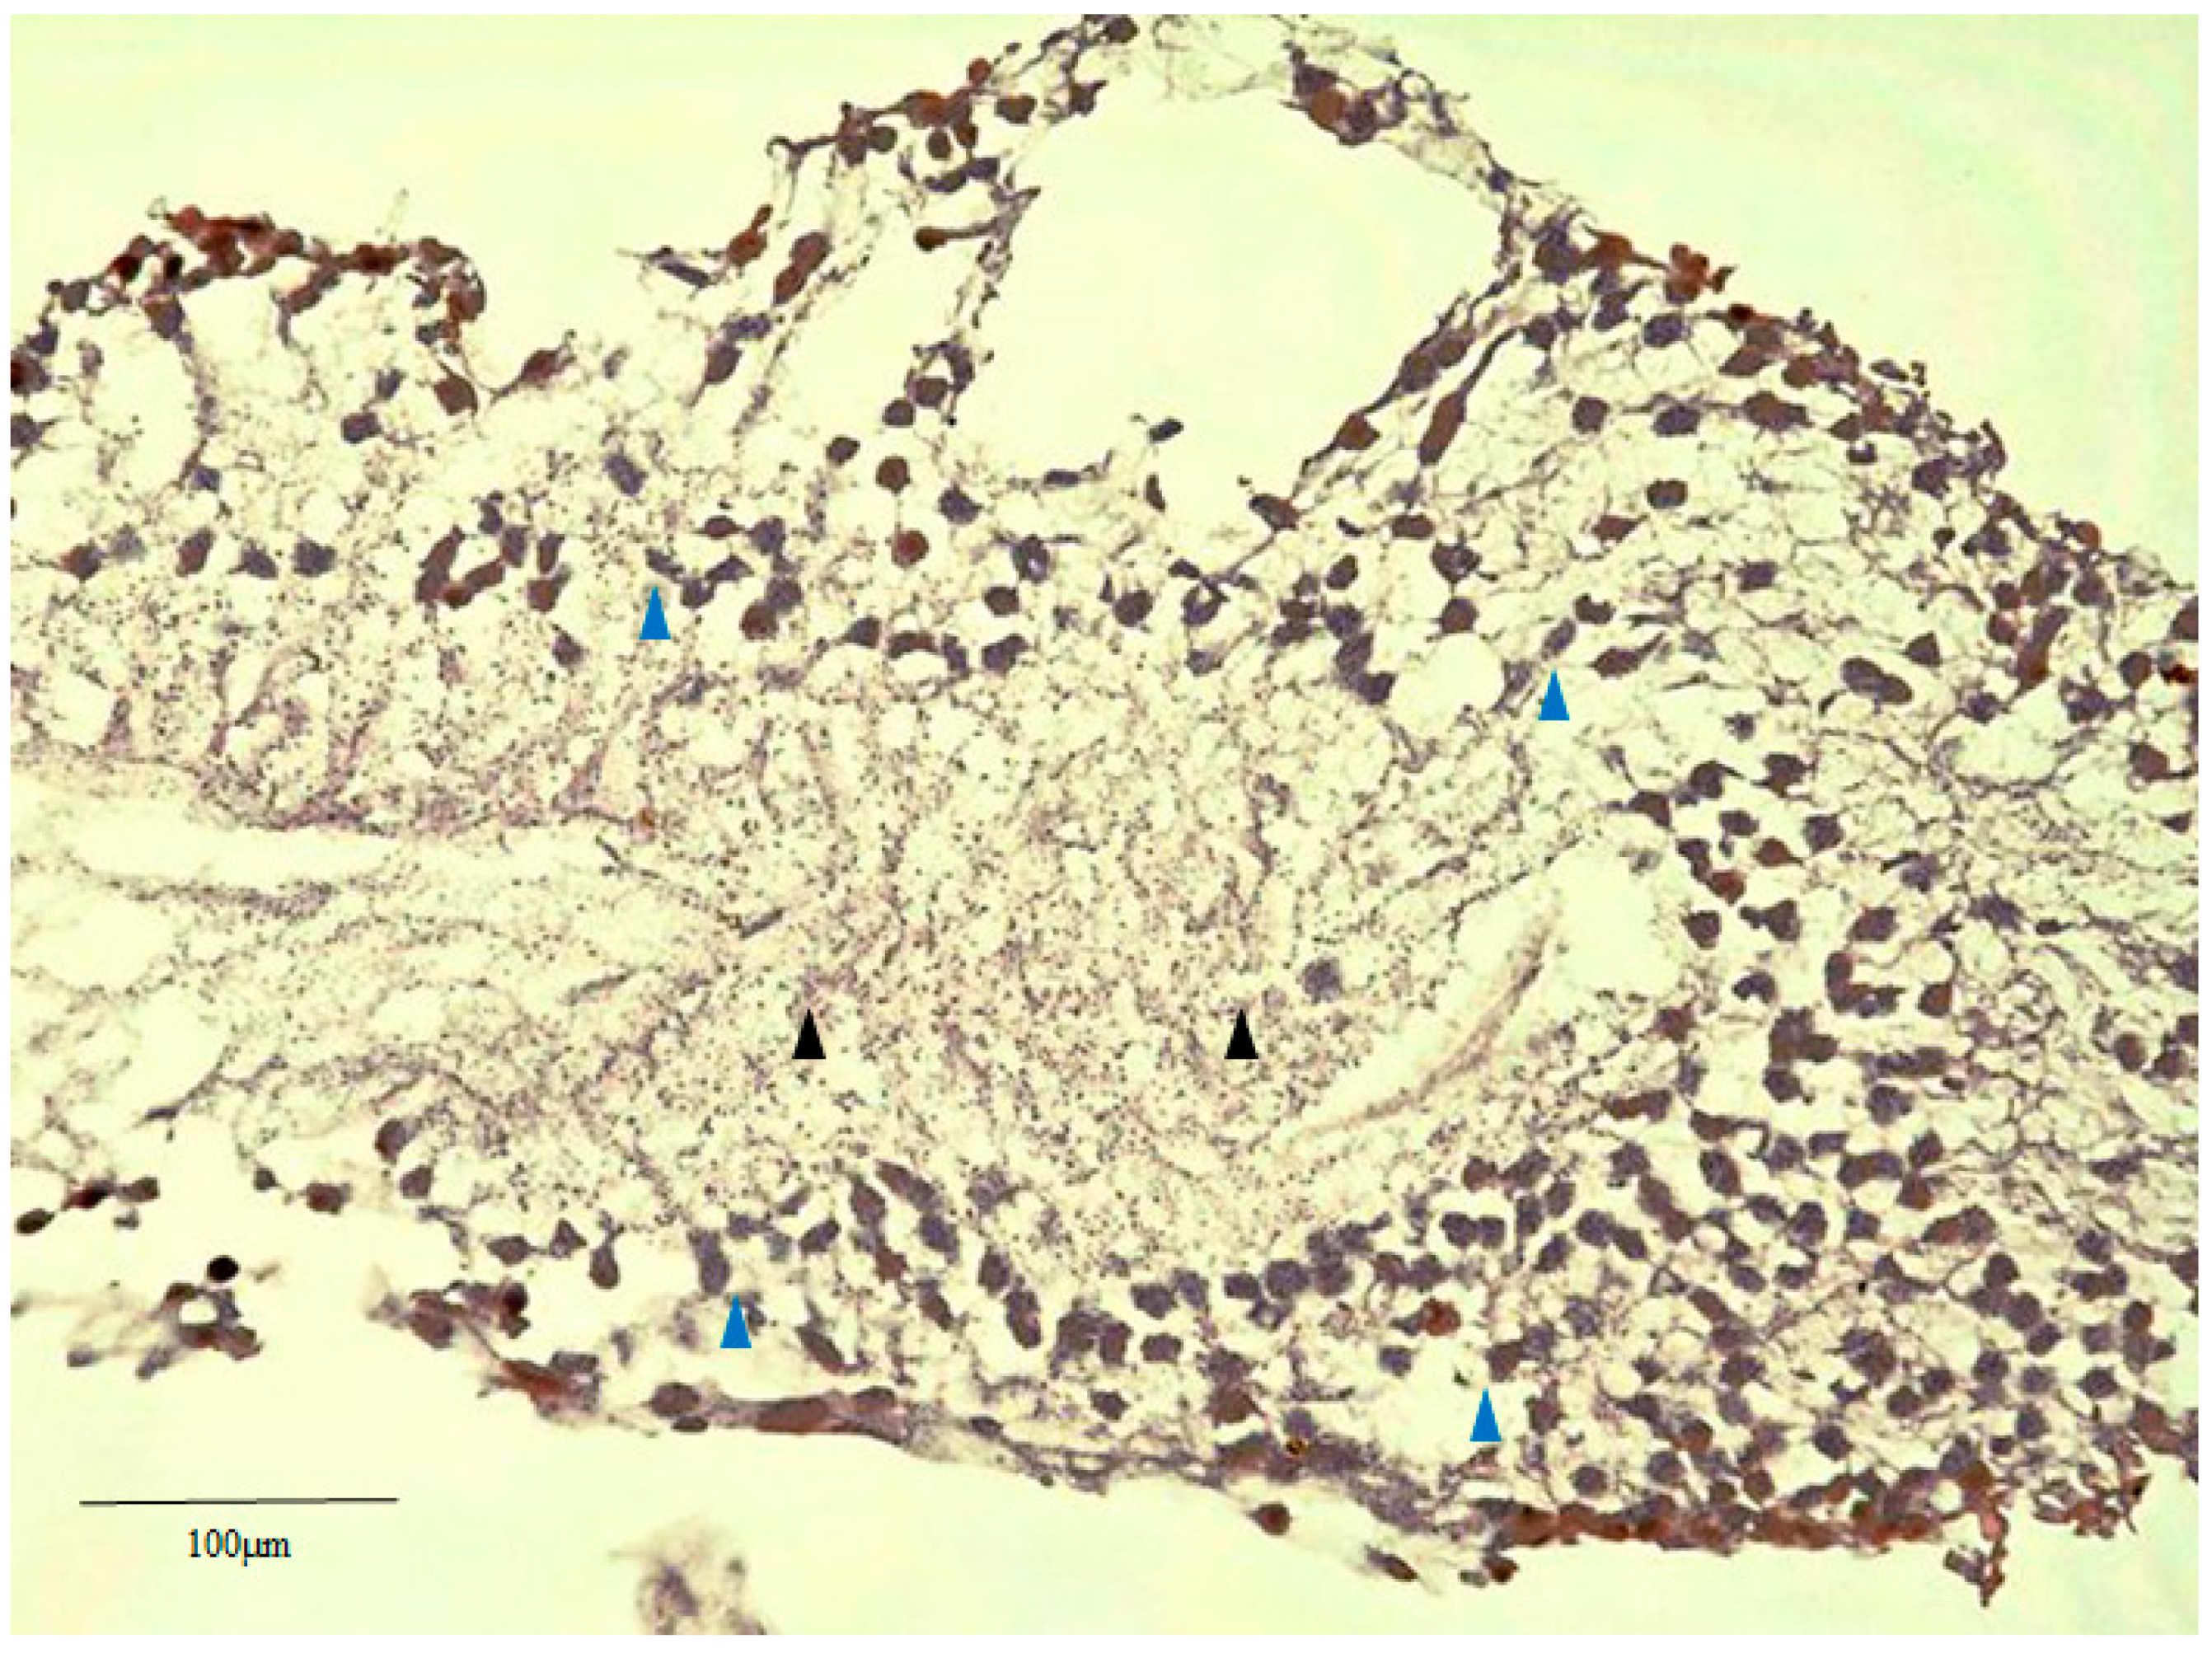

2.3. Glial Fibrillary Acidic Protein (GFAP), RPE65, and CK Immunostaining of the Human Retinal Lattice Degeneration Specimens